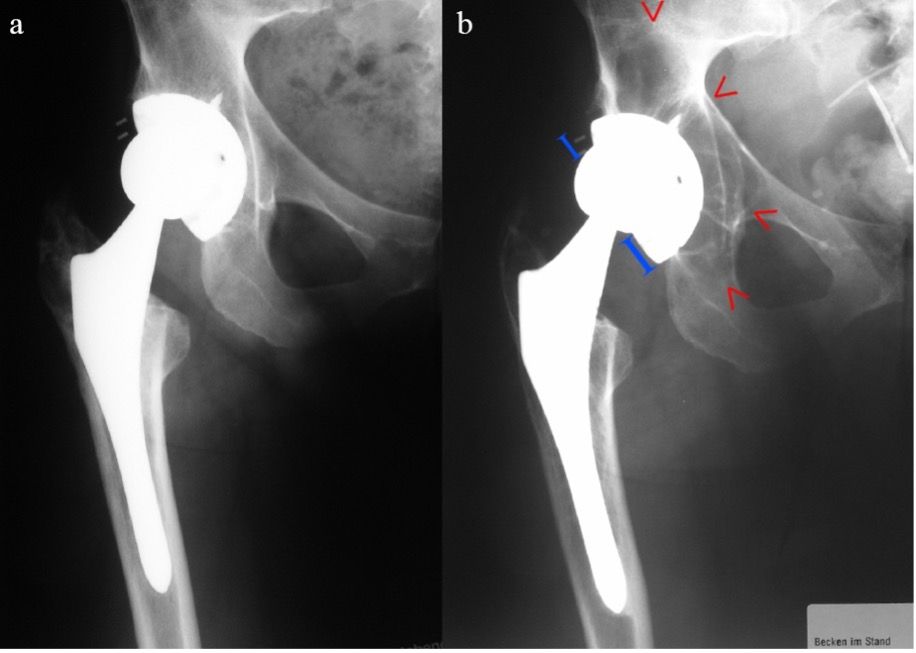

The unenhanced follow-up X-ray images (see Fig. 7) shows good bone fusion of the inserted bone in 2006 at the 4-year interval, with normally positioned acetabular component without evidence of loosening. As early as 2010, at the 8-year interval, osteolysis of the superolateral acetabular teardrop is obvious, with a lysis margin along the acetabular dome screw and visible backtwist of the dynamic hip screw (at-risk implant). The next visit of the patient was only arranged in 2020 with suspected symptomatic loosening of the indwelling acetabular component on the right. The unenhanced X-ray follow-up image confirmed this suspicion and presented with complex findings (see Fig. 7).

In order to clearly identify this defect and to plan the intraoperative procedure, an organized procedure as specified by ADC is the obvious approach. The diagnostic process is illustrated with an example in Figure 8. Figure 9 also shows the involvement of the posterior acetabular column in the CT imaging.

In summary, this shows a high-grade Type 3 C defect. According to the therapeutic ADC algorithm, this requires revision with metallic augmentation in the load-bearing zone of the superolateral and dorsal acetabular rim. Since this is a bony defect of >10 mm, an anatomical ileum tension band should be used for additional stabilization and preventing major relative movements. In our procedure, a modular support cup is used to meet the requirements with a caudal hook and the option of intraoperative adjustment with various augmentations and tension bands [10]. In addition, debrided bone defects should be augmented with biological material using impaction bone grafting outside of the loadbearing areas of the acetabular rim.